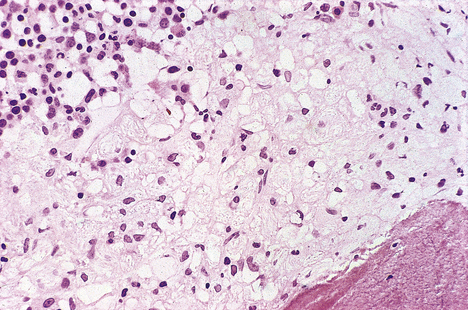

In this condition the calcium salts are precipitated on to connective tissue fibres (e.g. collagen, elastin; Fig. 7.11).

image

Fig. 7.11 Calcification of alveolar walls. The purple-staining material deposited on alveolar walls is calcification in a patient with hypercalcaemia.